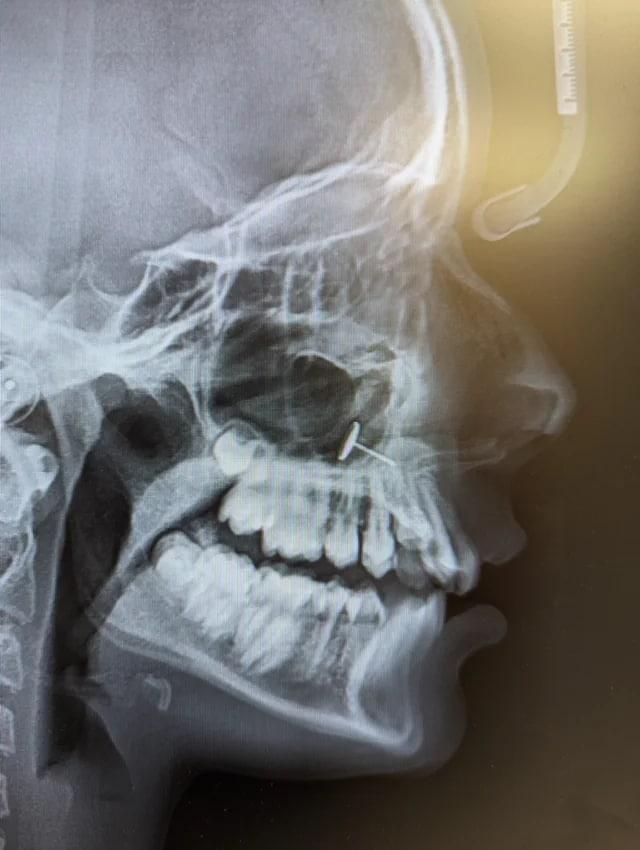

X레이에 찍힌 콧속 금속에 깜짝…그렇게 6개월 지낸 13살 소녀